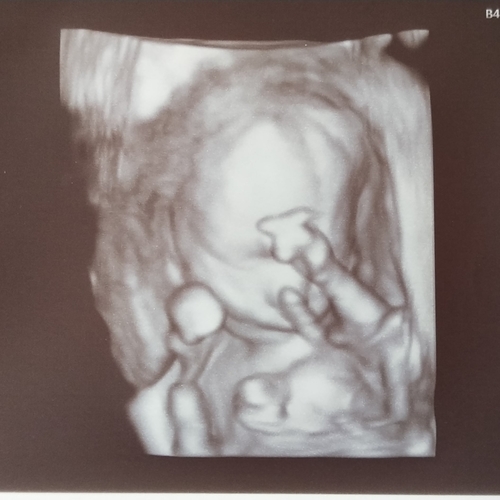

Vanmorgen ook de 20 weken echo gehad en bij ons was gelukkig ook alles goed. Was behoorlijk nerveus maar de kleine meid groeit goed en het zag er allemaal goed uit gelukkig🥰

26 maart een perfecte 20 weken echo gehad 🥰 ze zat zelfs boven het gemiddelde moest tussen de 350 gram en 400 gram zijn en ze was 409🥰 en ze had hele grootte voetjes bijna 36 mm 😂 al met al ik kan niet wachten om haar 23 april weer te zien!

Ik heb morgen eind vd middag de 20 weken echo en mijn vriend blijft in de auto met de ipad om te videobellen. Ben mega nerveus😔 hoop zo dat alles goed is met ons kleine meisje.. Ik hou me maar vast aan het feit dat de nipt en 15 weken geslachtsbepalings echo super goed waren en goed op groei en ze al best wat konden zien aan vloeistoffen in de blaas en maag en hersenhelftjes goed verdeeld. Maar pff wat mis ik de controle bij de verloskundige om even het hartje te horen. Ook al voel ik haar elke avond kriebelen.🙈 Ben blij als morgen voorbij is en ik een beetje zekerheid heb hopelijk! 🙏